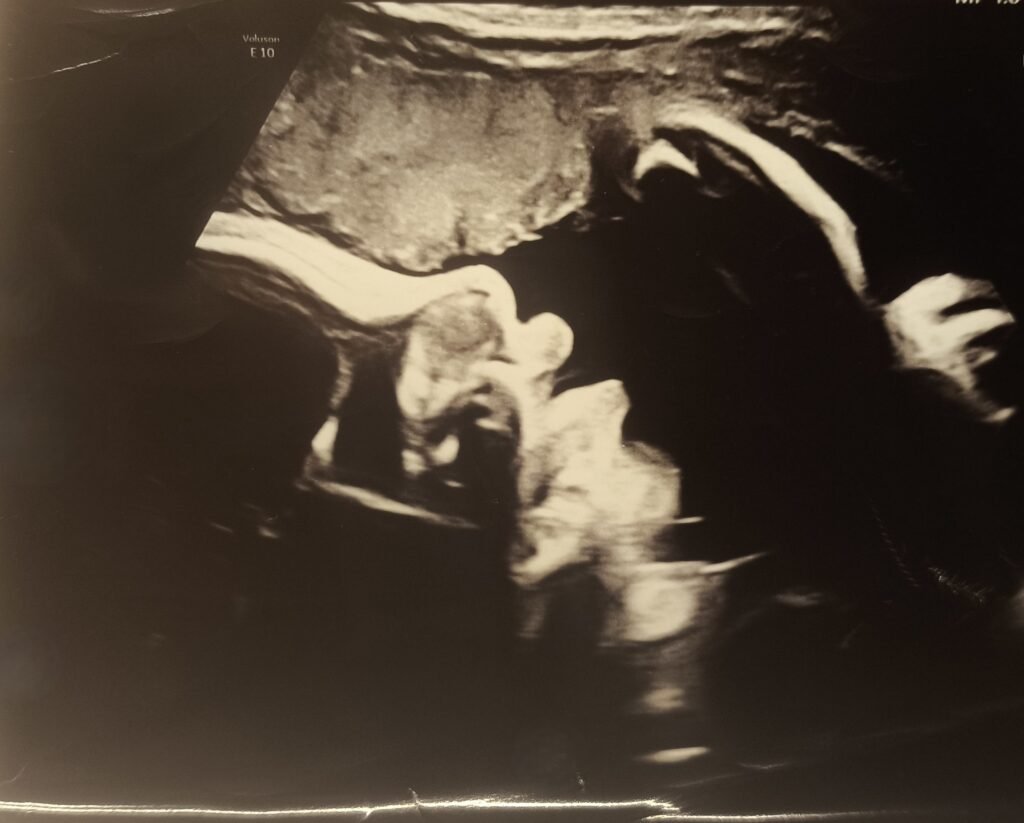

Anatomy scan – Week 20

04/11/2025

We are halfway. Time for another ultrasound. If you assume, half baked is half a baby you are sorely mistaken. During the 20-week scan we got to see organs, bones, blood flow through the heart and umbilical chord and so far everything looks as it should. The face profile shows us the cutest button nose and we can’t wait to meet our little munchkin. In the picture you can see the right foot.

Healthy baby, happy parents (for now…)